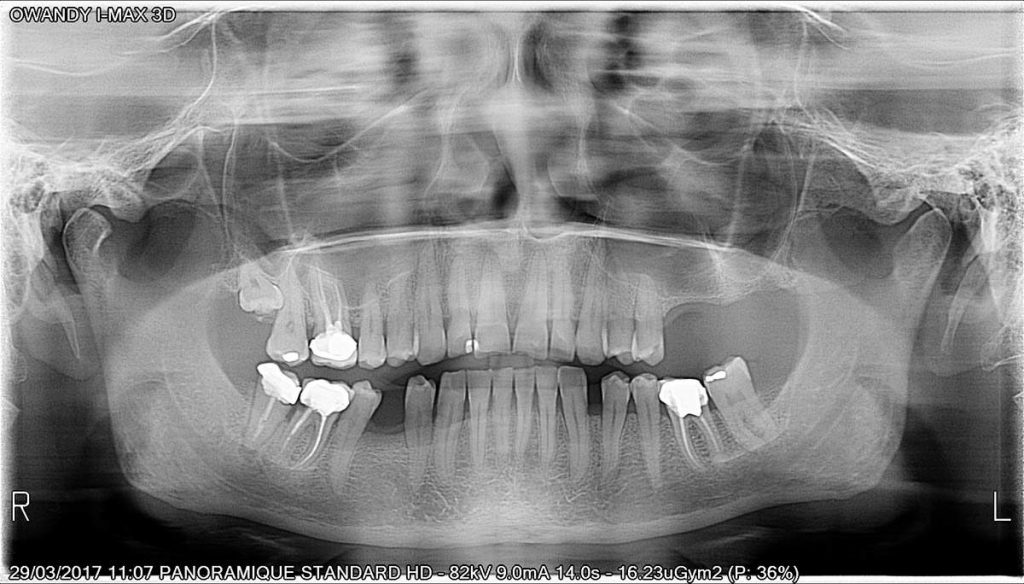

Calidad de imagen excepcional